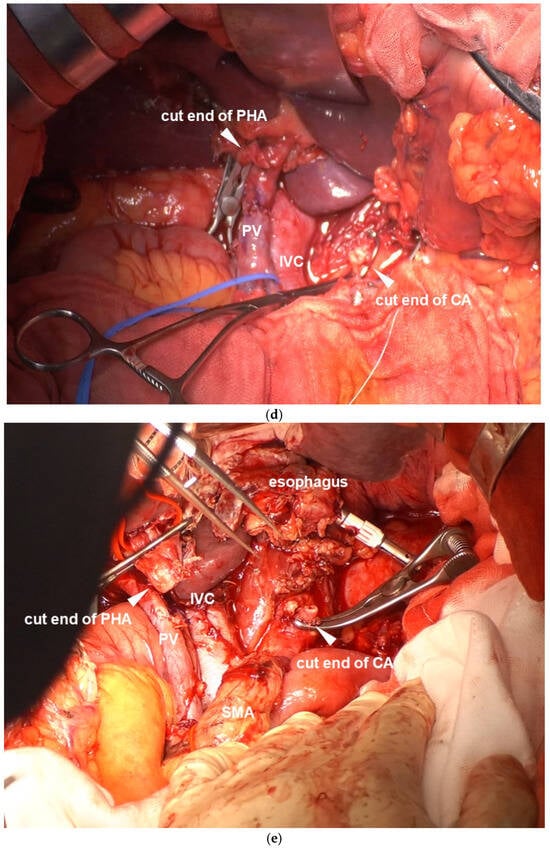

CA Reconstruction in TP-CAR+TG